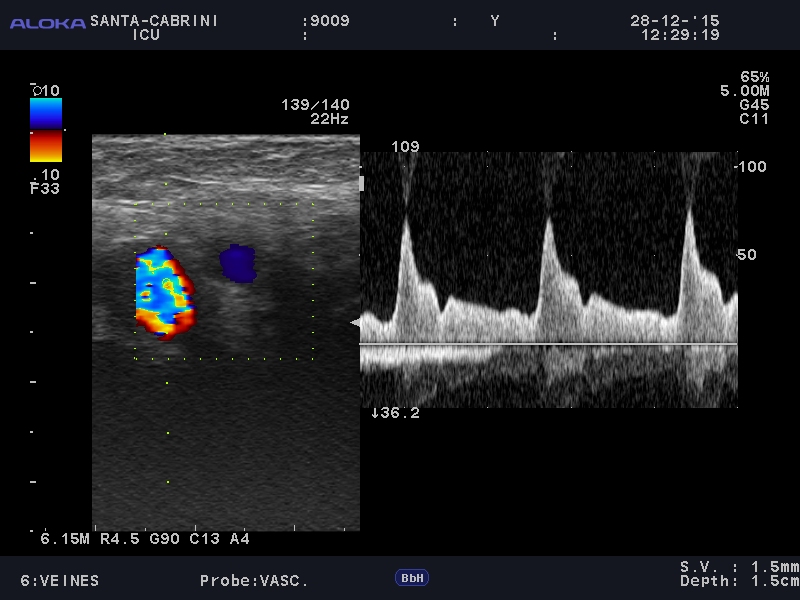

So this astute finding (as the requisition for a CT was being done) prompted me to do a little further neuro-ultrasound. Here is the distal carotid doppler:

So this is done in the upper neck, just distal to the bifurcation, so while extra cranial, the internal carotid nonetheless represents a view into the relationship between arterial flow and intracranial hemodynamics. It takes virtually no experience to see the radical difference in flow between the internal and the external carotid. The EC shows a beautiful systolic peak and diastolic flow. On the other hand, the IC shows a small systolic peak, a bit of retrograde flow, and essentially minimal or no diastolic flow. That is telling us, physiologically, that the ICP elevation has radically limited diastolic flow. This isn’t good.